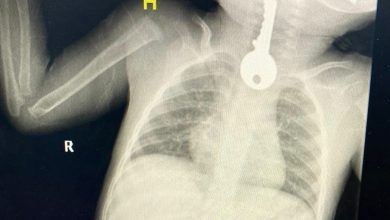

تدخل عاجل لاستخراج مفتاح من مريء طفل #عاجل

تمكن فريق طبي في محافظة الطائف من إنقاذ طفل كاد أن يفارق الحياةبعد أن أحضر إلى قسم الطوارئ في حالة…